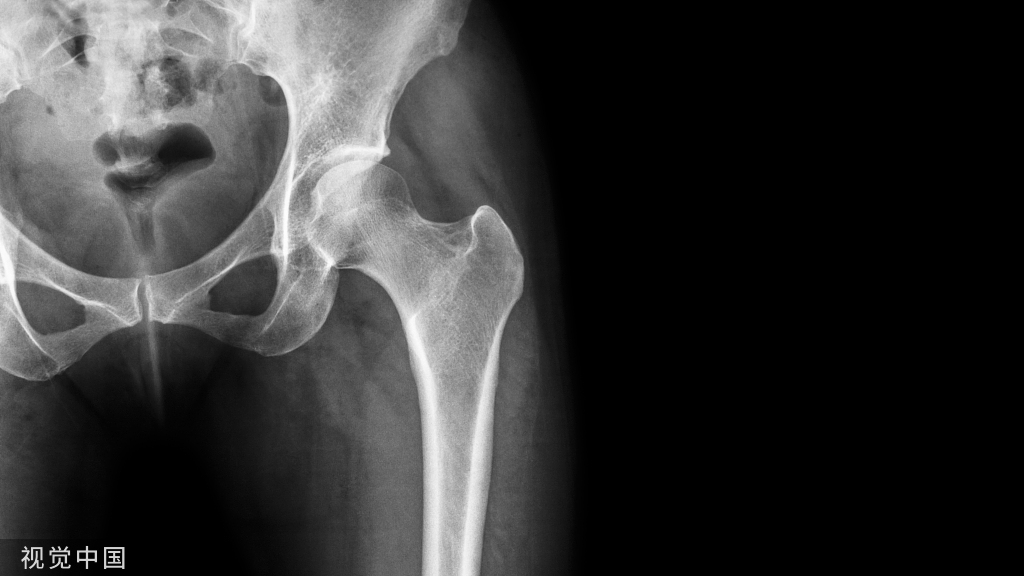

根据植骨需要的大小、形状,可在髂骨的不同部位采取。条状骨片可用骨刀沿髂嵴作平行方向切取。如需要薄的大片皮质骨,可在髂骨外板采取。

先按计划取骨的大小,在四周用骨刀轻轻切开,然后轻轻在内、外板间插入骨刀撬开,即可取出。楔状骨块可用骨刀或电锯在全厚的髂骨嵴上切取。

如需要碎骨片或骨条植骨,可用骨凿或弧形凿从髂骨翼外板取骨。在切除髂嵴后,可用刮匙插入髂骨内、外侧骨皮质骨板中间的骨松质间隙中刮取较多骨松质。从髂骨外板切取骨皮质时,先以骨凿或动力锯切割出取骨范围,然后再以宽骨凿轻撬取下骨块。